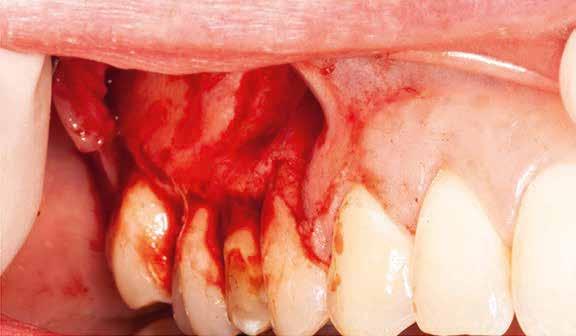

A beavatkozás során helyi érzéstelenítésben teljes vastagságú mucoperiostealis lebenyt képeztünk, és a sablon segítségével bejelöltük a preparálandó csontablak határait. Az ablak széleinek megfelelően Piezotome CUBE LED kézi-darabbal (ACTEON) a kortikális teljes vastagságában vágást ejtettünk, majd az így kapott csontlemezt (ablakot) eltávolítottuk (1. e–h. ábra), és ezt követően steril fiziológiás sóoldatba helyeztük. A rezekció elvégzését követően (1. i. ábra) a mezialis csatornákat ultrahangos eszközök segítségével (NSK) retrográd irányból preparáltuk, majd az így kialakított mélyedésbe retrográd gyökértömést készítettünk. A tömés anyagául az EndoSequence BC RRM Fast Set Putty-t (Brasseler) választottuk. A tömés elkészítését követően a csontablakot visszaillesztettük, és a stabilizálása érdekében a vágásoknak megfelelően kialakult résekbe kollagén szivacsokat (Collagen Tape, Zimmer Biomet) helyeztünk (1. j-k. ábra). A lebenyt 6/0-s Prolene varratokkal (Corpaul) rögzítettük.

A kétéves kontroll során elvégzett klinikai és radiológiai vizsgálat (CBCT-felvétel) a periapicalis elváltozások megszűnését és a corticalis csontállomány tünet- és szövődménymentes gyógyulását